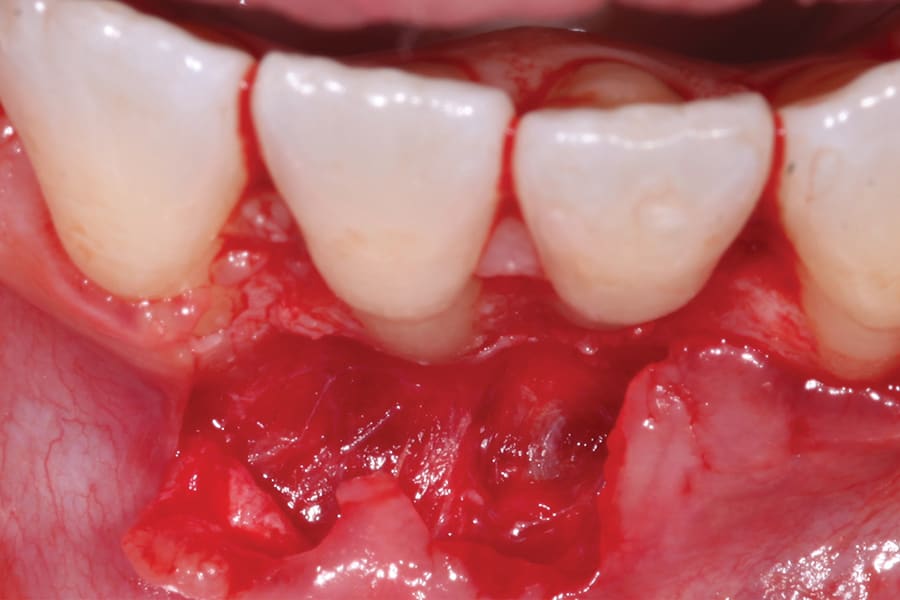

A second option is to use corrective orthodontic therapy in the form of fixed appliance application to torque the root back into the correct position (Figure 5 through Figure 7). This requires full-sized archwire insertion into a precision edgewise bracket (Figure 7). This can be a time-consuming undertaking, as the step-up through various archwires until fully engaging a full-sized wire will take a few months. Nevertheless, significant corrective changes often can be observed, as the tooth's investing structures often spontaneously remodel, at least partially, in response to the corrected tooth position (Figure 5 and Figure 7, Figure 11 and Figure 13).

A third option for correcting tooth position is via orthodontic aligner therapy (Figure 8 through Figure 13). With this modality, precise 3-dimensional control must be designed and incorporated into the aligner prescription. This option presents a more expedient alternative than the use of conventional fixed appliances, because the aforementioned stepwise progression of increasing the size of archwires is unnecessary, and corrective force can be applied from the onset (Figure 12). Significant overcorrection of the intended movement is recommended in the prescription. In this way, if the aligners do not fully express the movement, continued usage of them may accomplish it. Should the result be attained prior to the conclusion of all aligners, cessation (and more appropriate retention) is indicated.

Although spontaneous improvement of the investing tissues is often observed through orthodontic correction (Figure 7 and Figure 13),5 additional corrective action is frequently indicated afterwards, particularly when cosmetics are to be considered. A recession defect case is depicted in Figure 17 through Figure 26 in which corrective action was necessary and accomplished through aligner therapy followed by connective tissue grafting.6 It should be noted that although this corrective scheme may successfully achieve an acceptable cosmetic and functional result, it is not likely a regenerative outcome in the sense that a previously dehisced root surface typically will not attain ligamentous insertion into freshly laid cementum. A long junctional epithelium or connective tissue attachment at best is the more likely outcome. Consequently, a preventive approach initially would be more desirable.